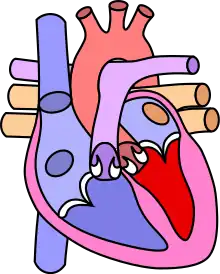

![]() | |

| Diagram of a healthy heart and one with tetralogy of Fallot | |